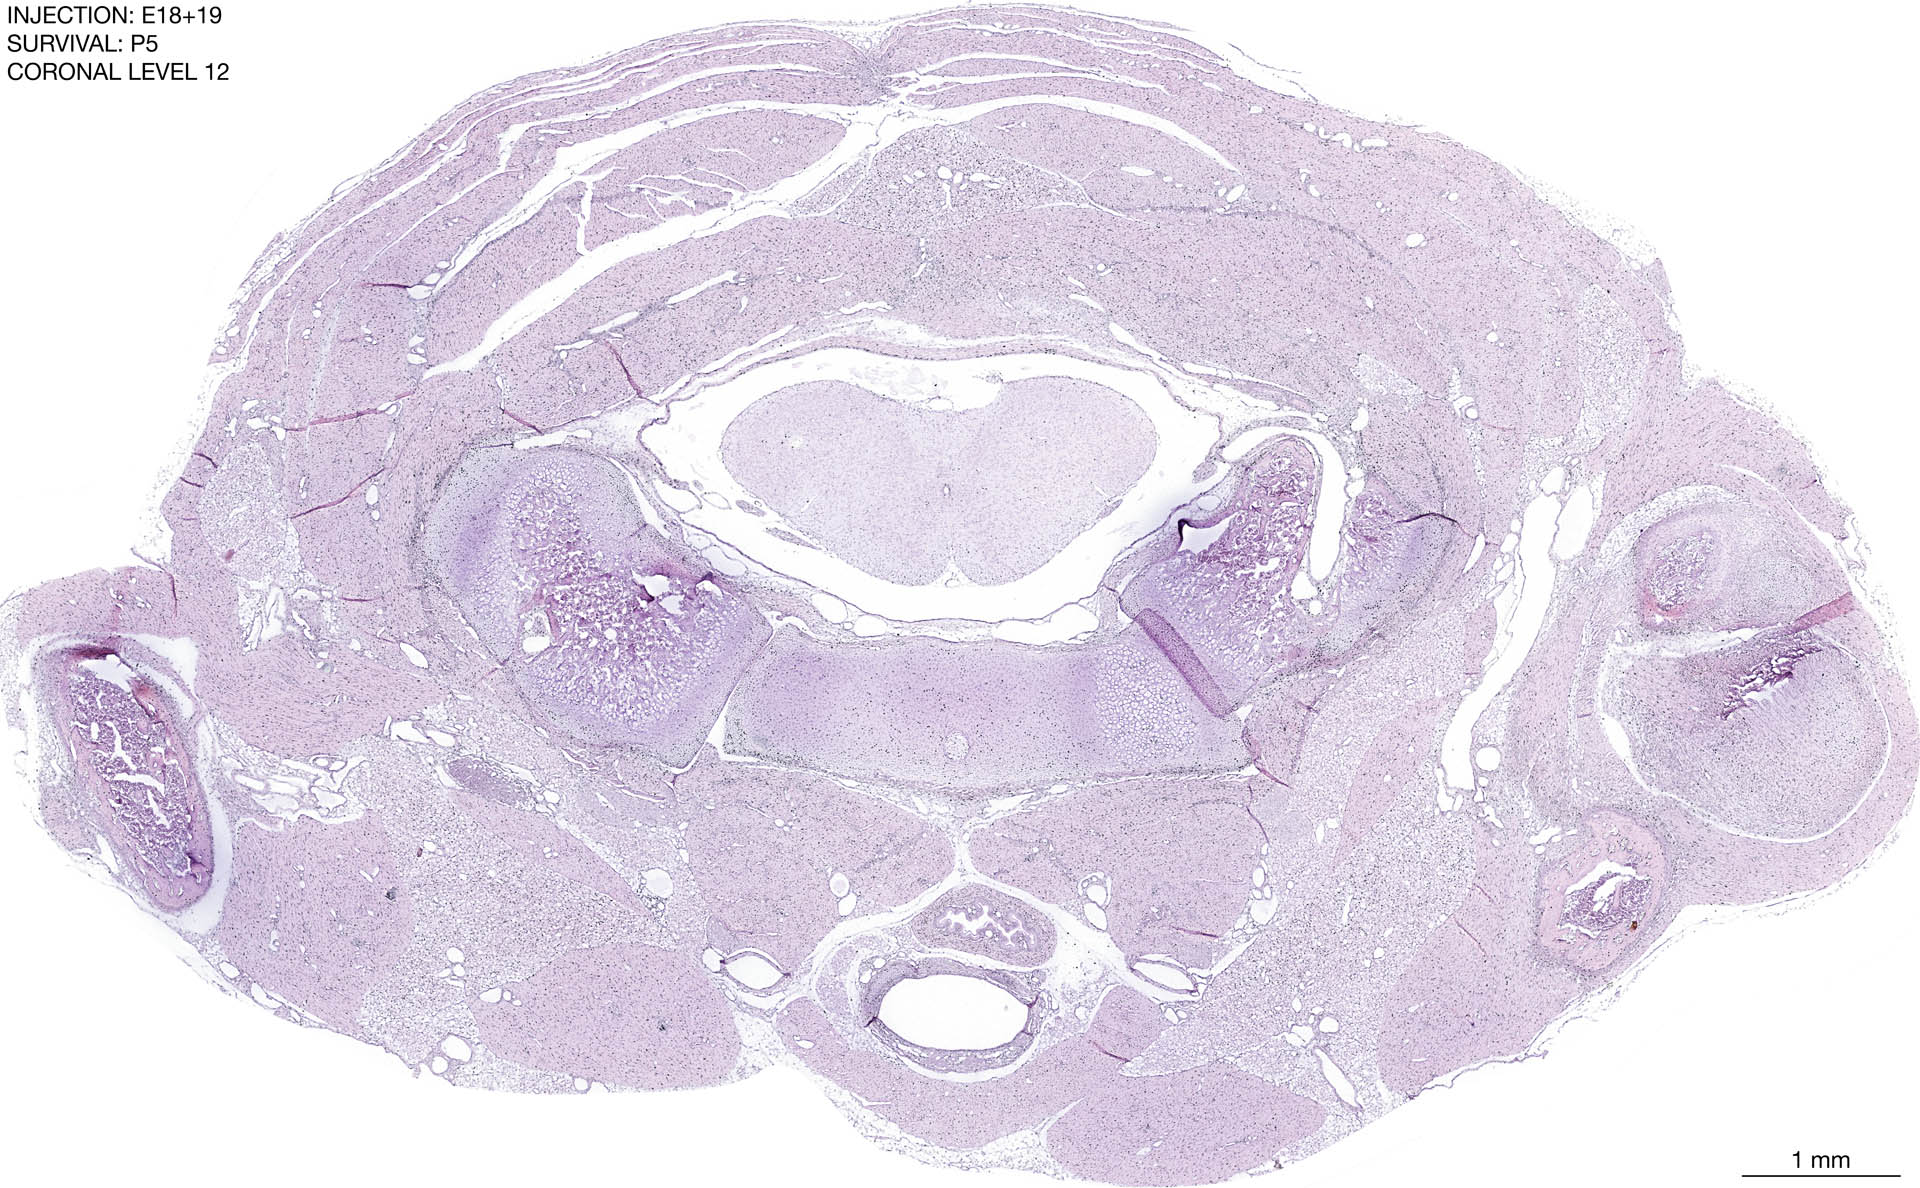

The images below are from the brain of a rat that was exposed to tritiated thymidine on E18+19 and survived to P5. Download: Large | High Res Download: Large | High Res Download: Large | High Res Download: Large | High Res Download: Large | High Res Download: Large | High Res Download: Large | High Res Download: Large | High Res Download: Large | High Res Download: Large | High Res Download: Large | High Res Download: Large | High Res Download: Large | High Res Download: Large | High Res Download: Large | High Res Download: Large | High Res Download: Large | High Res Download: Large | High Res Download: Large | High Res Download: Large | High Res Download: Large | High Res Download: Large | High Res Download: Large | High Res Download: Large | High Res